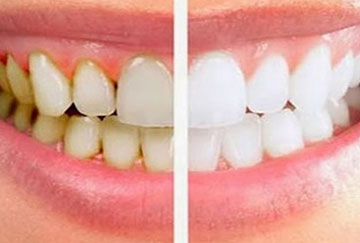

Plaques et tartre